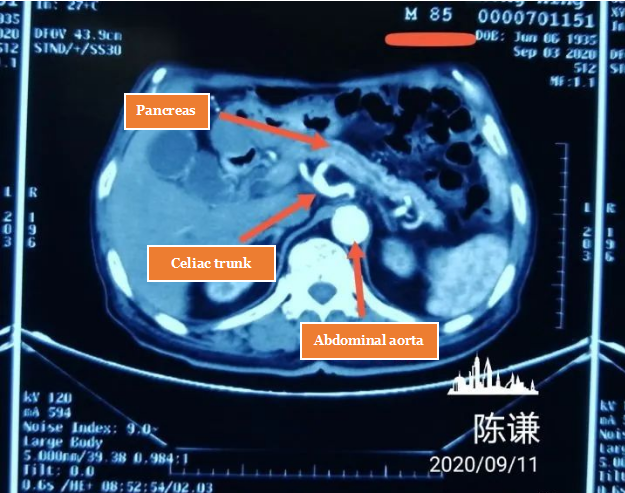

This is an 85-year-old patient who came from Tianjin and was diagnosed with pancreatic cancer.

The patient presented with abdominal pain and underwent examinations at a local hospital, which revealed a pancreatic tumor and elevated levels of CA199. After comprehensive evaluations at the local hospital, the clinical diagnosis of pancreatic cancer was established.

Taking into consideration the patient’s advanced age of 85 years, although there was no cancer metastasis, the limitations imposed by age meant that surgery, chemotherapy and radiation therapy were not feasible options for the patient. The local hospital was unable to provide effective treatment options, leading to consultations and negotiations that resulted in the patient being transferred to our hospital. Eventually, a decision was made to proceed with a High-Intensity Focused Ultrasound (HIFU) ablation treatment. The procedure was performed under sedation and analgesia, and the surgical outcome was favorable, with virtually no noteworthy discomfort experienced by the patient on the second day post-surgery.

Postoperative examinations revealed more than 95% ablation of the tumor, and the patient showed no signs of abdominal pain or pancreatitis. Consequently, the patient was able to be discharged on the second day.